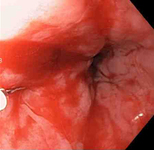

Laceração de Mallory Weiss com sangramento observada em retroflexão

Do acervo pessoal de Douglas Adler; usado com permissão